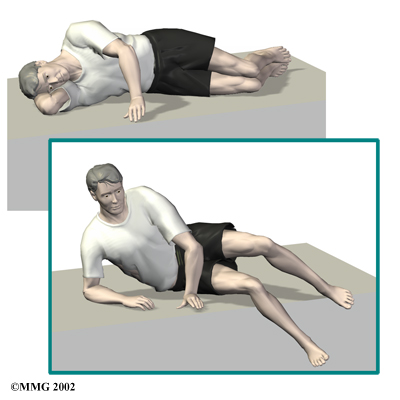

When you begin Chiropractic at Active Therapeutic Solutions, we may prescribe ways to immobilize the spine. Keeping the back still for a short time can calm inflammation and pain. Patients may find that curling up to sleep or lying back with their knees bent and supported gives the greatest relief. These positions flex the spine forward, which widens the spinal canal and can ease symptoms.

The Chiropractors at Active Therapeutic Solutions also guide patients in a program of exercise designed to widen the spinal canal and take pressure off the spinal nerves. After evaluating your condition, we can assign positions and exercises to ease your symptoms.

The Chiropractors at Active Therapeutic Solutions also guide patients in a program of exercise designed to widen the spinal canal and take pressure off the spinal nerves. After evaluating your condition, we can assign positions and exercises to ease your symptoms.